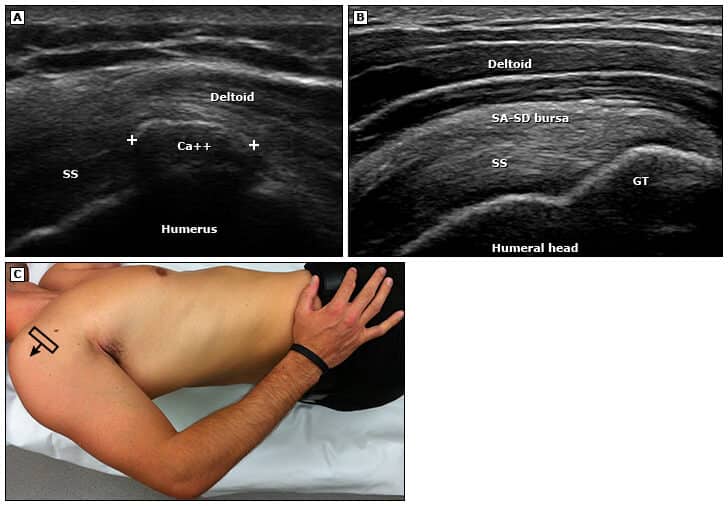

As radiografias simples do ombro normalmente não apresentam sinais de tendinopatia do manguito rotador e não são recomendadas de forma rotineira. No entanto, podem ser úteis para identificar condições associadas, como artrite ou calcificação dos tendões, para os casos onde há resposta insuficiente ao tratamento conservador, tendinopatia recorrente ou, ainda, antes de injeções articulares (embora a ultrassonografia guiada seja mais precisa).

No diagnóstico por ultrassom para a síndrome do manguito rotador, as alterações podem incluir:

- Infiltração de gordura.

- Impacto durante o exame sonoro.

Realização do exame de ultrassom

A visualização adequada dos tendões exige um bom posicionamento do paciente (posição de Crass) e do transdutor, ajustes corretos no equipamento de ultrassom e manobras dinâmicas para obter as melhores imagens.

A posição de Crass ideal, por sua vez, pode ser difícil em pacientes com dor, mas é possível facilitar a manutenção dessa posição pedindo ao paciente para simular o ato de pegar uma carteira no bolso de trás e sentar-se sobre a mão, utilizando o peso corporal.